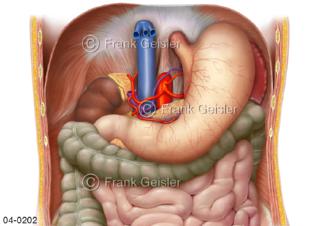

Bildergalerie Topografie Organe

Bilder zur topografischen Anatomie, die Lage der Organe und die Strukturen nach ihren räumlichen Lagebeziehungen zueinander, Übersicht der inneren Organe im Kopf und im Rumpf, Topografie der Organe im Brustraum (Thorax) und im Bauchraum (Abdomen)